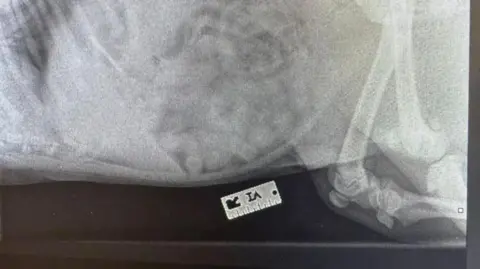

"They do all sorts of strange stuff, but this was a first for me," he said of the blade, adding it had shown up clearly on X-ray because it was metal.

Charlie was sedated and the object was surgically removed as there was no guarantee it could pass through him without coming free from its case.